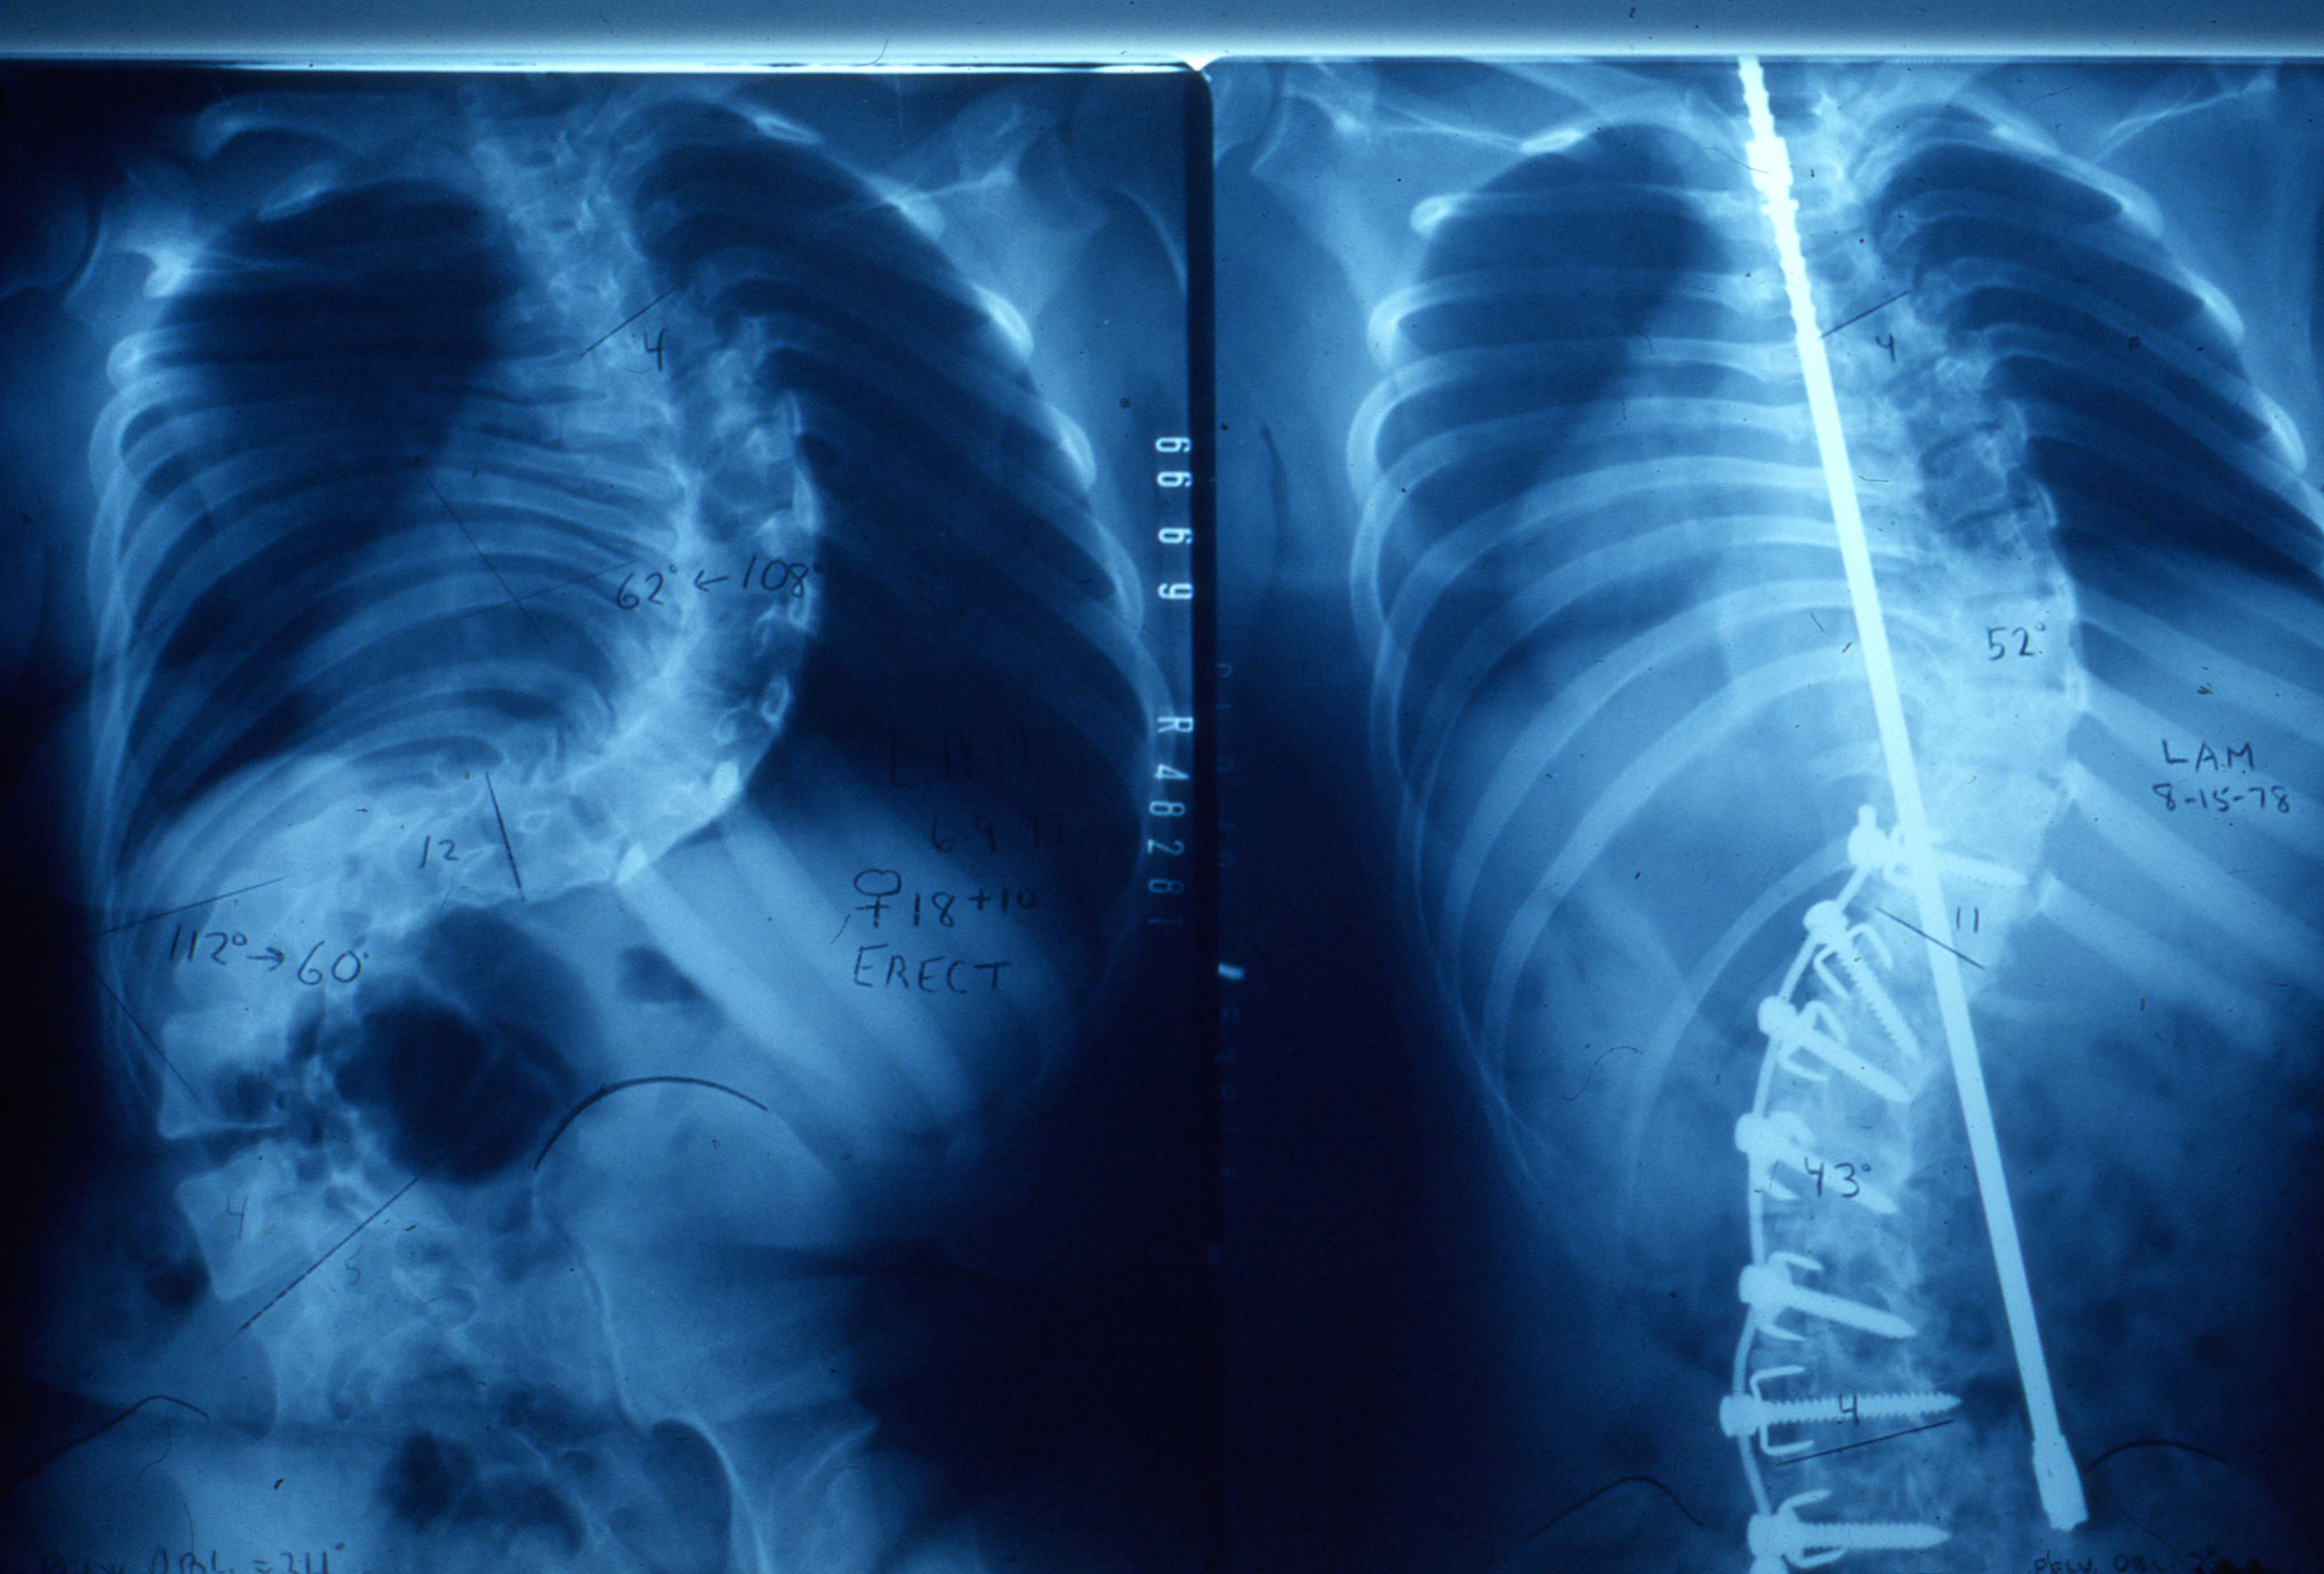

矯正前(左)、後(右)的X光片對照